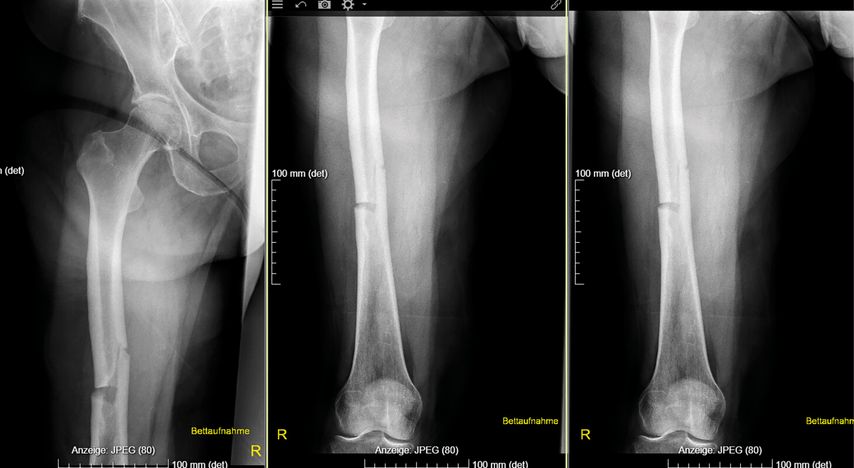

Dr. Bernhard Rintelen von der 2. Medizinischen Abteilung am NÖ. Landesklinikum Weinviertel/Stockerau präsentierte den Fall einer 72-jährigen Patientin mit Zustand nach Hysterektomie mit Salpingektomie sowie nach einem nicht metastasierten Kolonkarzinom. Nach einer Netzhautablösung bestand eine deutliche Visusbeeinträchtigung; bei Vorhofflimmern wurde die Patientin mit einem DOAK antikoaguliert. Die Familienanamnese war hinsichtlich Frakturen unauffällig. Mit 70 Jahren hatte die Patientin eine Femurfraktur erlitten. Die aktuelle Vorstellung erfolgte aufgrund multipler Wirbelkörperfrakturen sowie einer niedrigtraumatischen Sakrumfraktur. In der Bildgebung zeigten sich innerhalb weniger Monate wiederholt neue Einbrüche weiterer Wirbelkörper, das Labor war unauffällig. Eine Osteoporose war bekannt, insgesamt hatte die Patientin über 14 Jahre Bisphosphonate erhalten (9 Jahre oral, 5 Jahre Ibandronat i.v.). Eine osteoanabole Therapie war geplant; Teriparatid wurde aufgrund der Visusprobleme abgelehnt, weshalb eine Behandlung mit Romosozumab erfolgte. Nach einem Jahr zeigte sich eine Konsolidierung ohne weitere Wirbelkörperfrakturen.